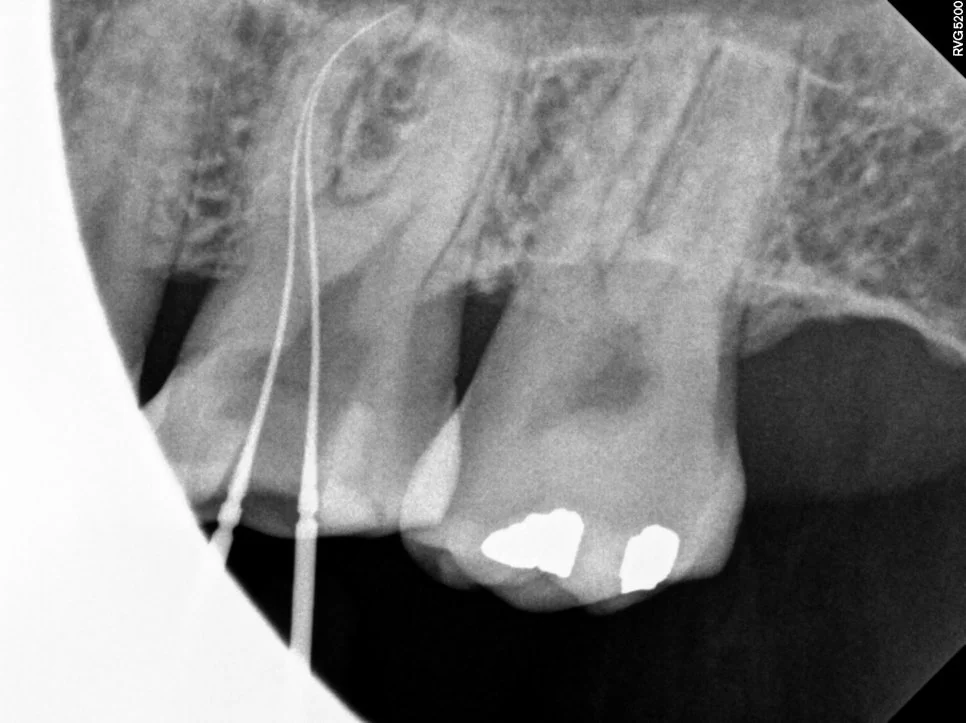

4번째 신경관이 보여 길을 찾아보았습니다. 같이 주행하는 것처럼 보이시나요?^^

약간 다른 각도로 촬영해 보니 두 개의 신경관이 각기 다른 길로 주행하고 있습니다. 이런 치아에서 다른 하나의 신경관을 찾지 못했다면 신경치료 후 통증의 원인이 될 수 있습니다.